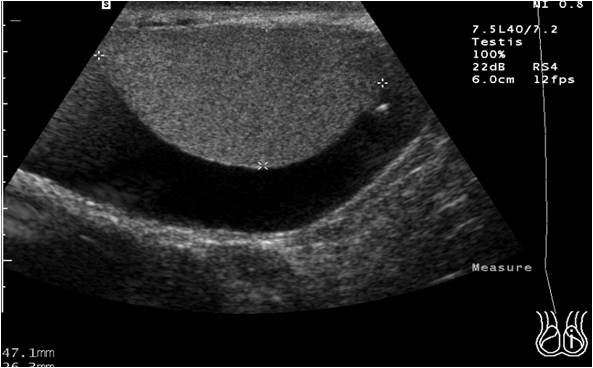

Finalmente tres estructuras que son complejas de ver en un solo corte, pero en este caso se ven, de medial a externo y de superficial a profundo:

Arteria Cubital, anecoica. Flecha amarilla.

Nervio Cubital, pegadito a ella, en forma de panal de abeja y ovalado. Flecha amarilla.

Más externo y profundo el Tendón Flexor Cubital del Carpo, con una forma ovalada, dispuesto en forma oblícua.